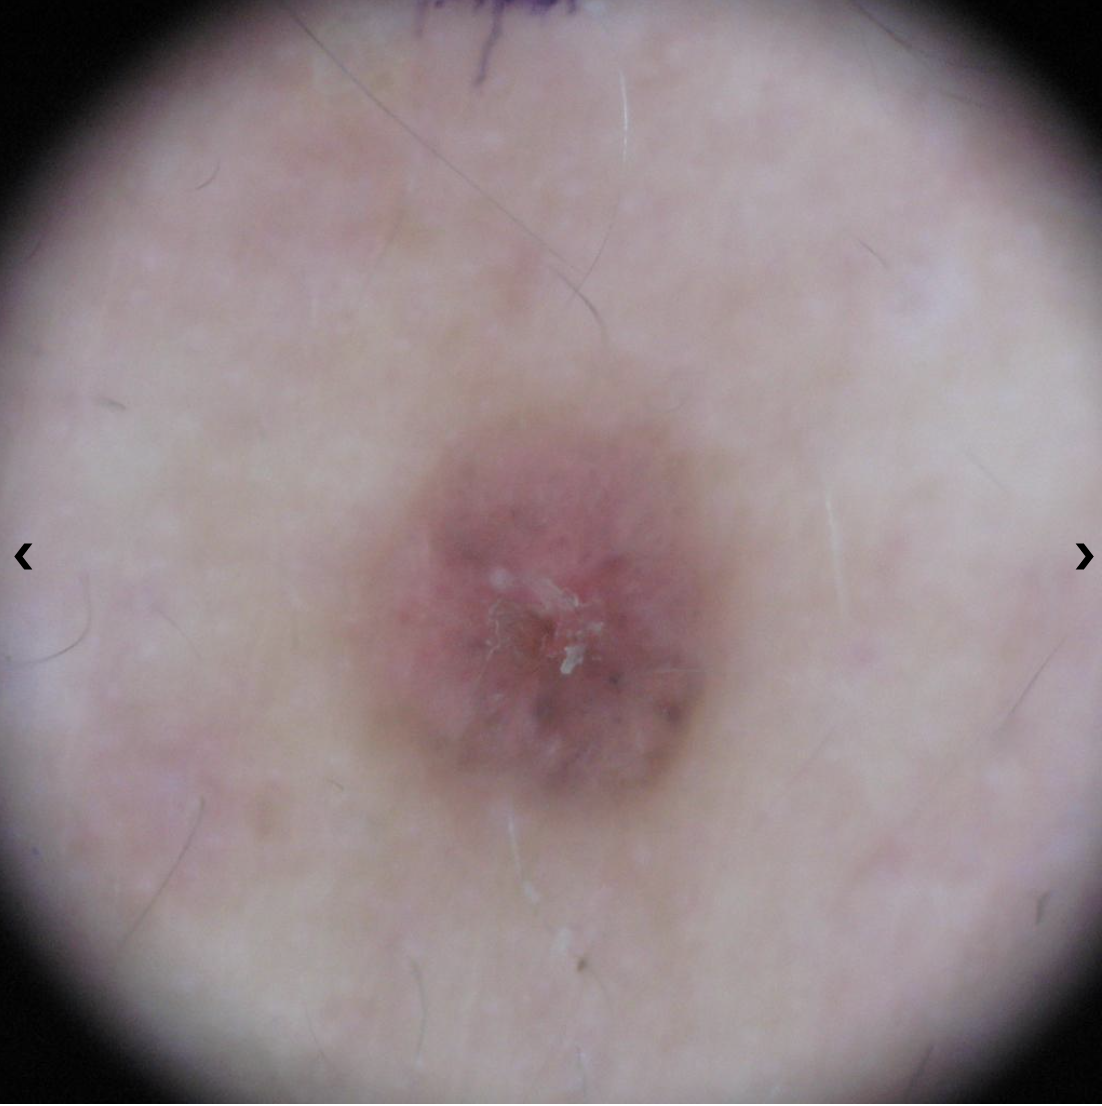

Basal cell carcinoma on the posterior torso. Photo: International Skin Imaging Collaboration at isic-archive.com